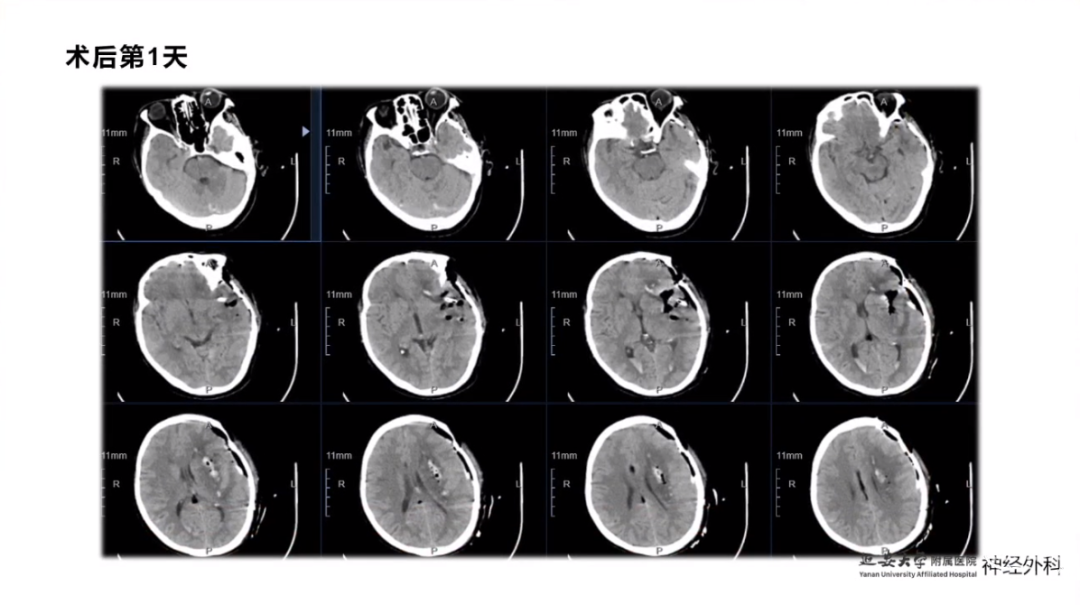

今天为大家分享的是《监测有道丨颅脑创伤-神经重症周刊》第337期,由延安大学附属医院神经外科贾云峰主任医师带来的:神经内镜为主导的多术式组合在重症脑出血中的应用,欢迎阅读、分享。

长期从事神经外科疾病的基础与临床研究。专长于神经急危重症综合治疗、神经内镜脑出血微创手术、脊髓脊柱疾病显微外科微创治疗、颅内及脊髓肿瘤、脑血管病、脑、脊髓先天畸形的微创治疗。参与主持完成科研项目《尼莫地平对脊髓损伤的作用研究》等,获陕西省自然科学优秀论文奖。参与国家卫健委牵头的《自发性脑出血的多中心登记研究》等项目研究及《脑出血患者颅内压监测》《脑出血后脑水肿的治疗》专家共识的制定。以第一作者在国内外发表核心期刊20余篇,SCI收录文章1篇,多次应邀在中华医学会、中国医师协会全国神经外科学年会交流发言。主编及参编著作3部,国家发明专利2项